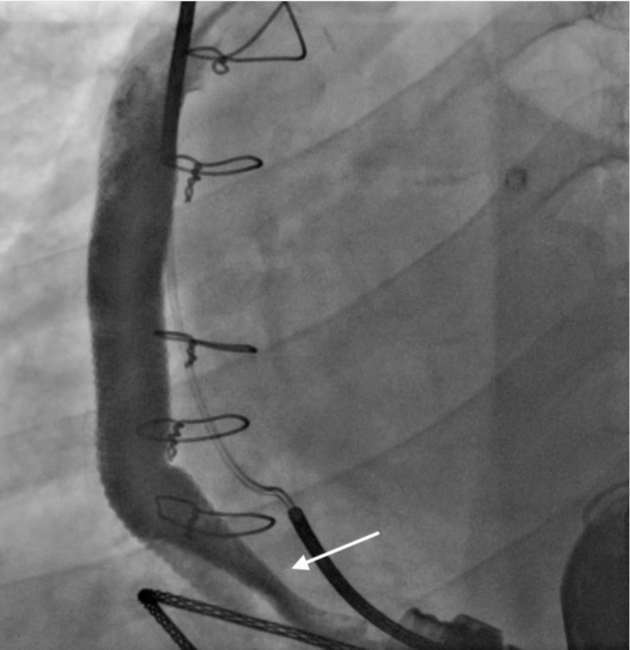

A 55-year-old male patient presented with a history of left ventricular assist device (LVAD) implantation due to ischemic cardiomyopathy. He was admitted to the cardiology department with progressive dyspnea. A HeartMate 3 (Abbott) had been implanted in the patient 3 years prior. Low-flow alarms were detected on the LVAD. An echocardiographic evaluation indicated enlargement of the left ventricle, aortic valve openings nearly in every beat, and deviation of the septum to the right. The lactate dehydrogenase (LDH) level was slightly elevated (355 U/L; normal range, 135-225 U/L). The patient was transferred to the catheterization unit to evaluate the outflow graft. The LVAD was temporarily stopped to demonstrate retrograde flow from the aorta through the outflow graft. Selective visualization was performed after engagement of a pigtail catheter in the outflow graft (Figure 1; Video Series). Twisting at the beginning of the outflow graft was clearly depicted. The patient underwent surgery to correct the twisting. The LVAD-graft junction area was reached with a left subcostal incision. The graft sheath was removed. Approximately 270° of rotation was detected at a distance of 10 cm from the LVAD (Figure 2). After correction, flow increased immediately back to normal levels.